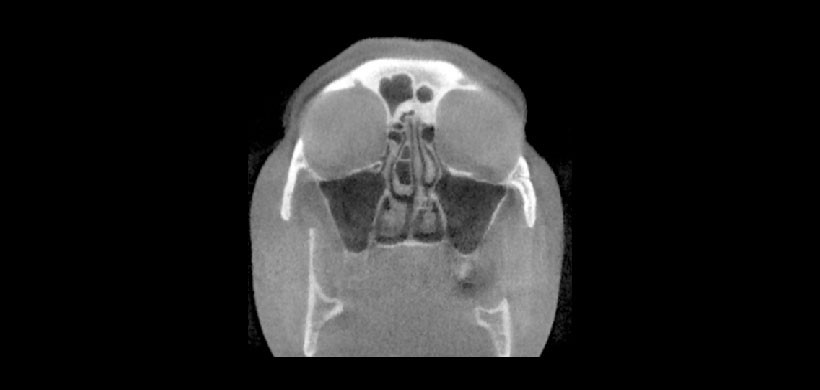

Fig 3. Tomografía volumétrica, vista coronal. Neumatización del proceso unciforme.